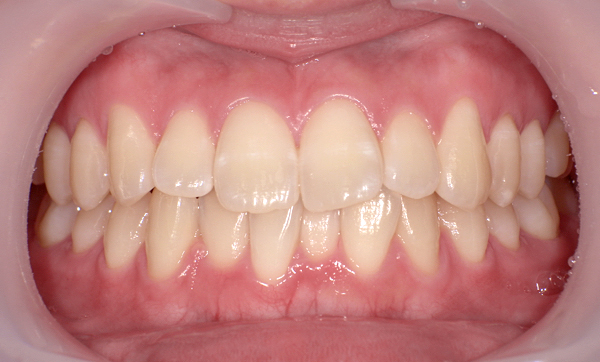

症例_009 「上下の前歯」症例

治療期間:7ヶ月金額:54万円+税20代女性捻転歯一部の反対咬合前歯のガタガタ

Before | After |

---|---|